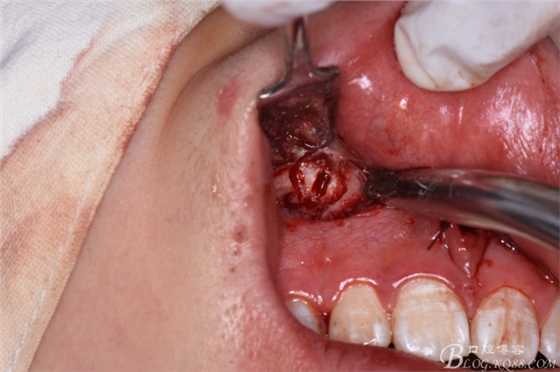

圖18.拔除大多生牙

圖20. 在12、13根尖所對應(yīng)的前廳溝處做第二個弧形切口

圖21.一定要切透粘骨膜。

圖22.翻瓣、暴露骨面